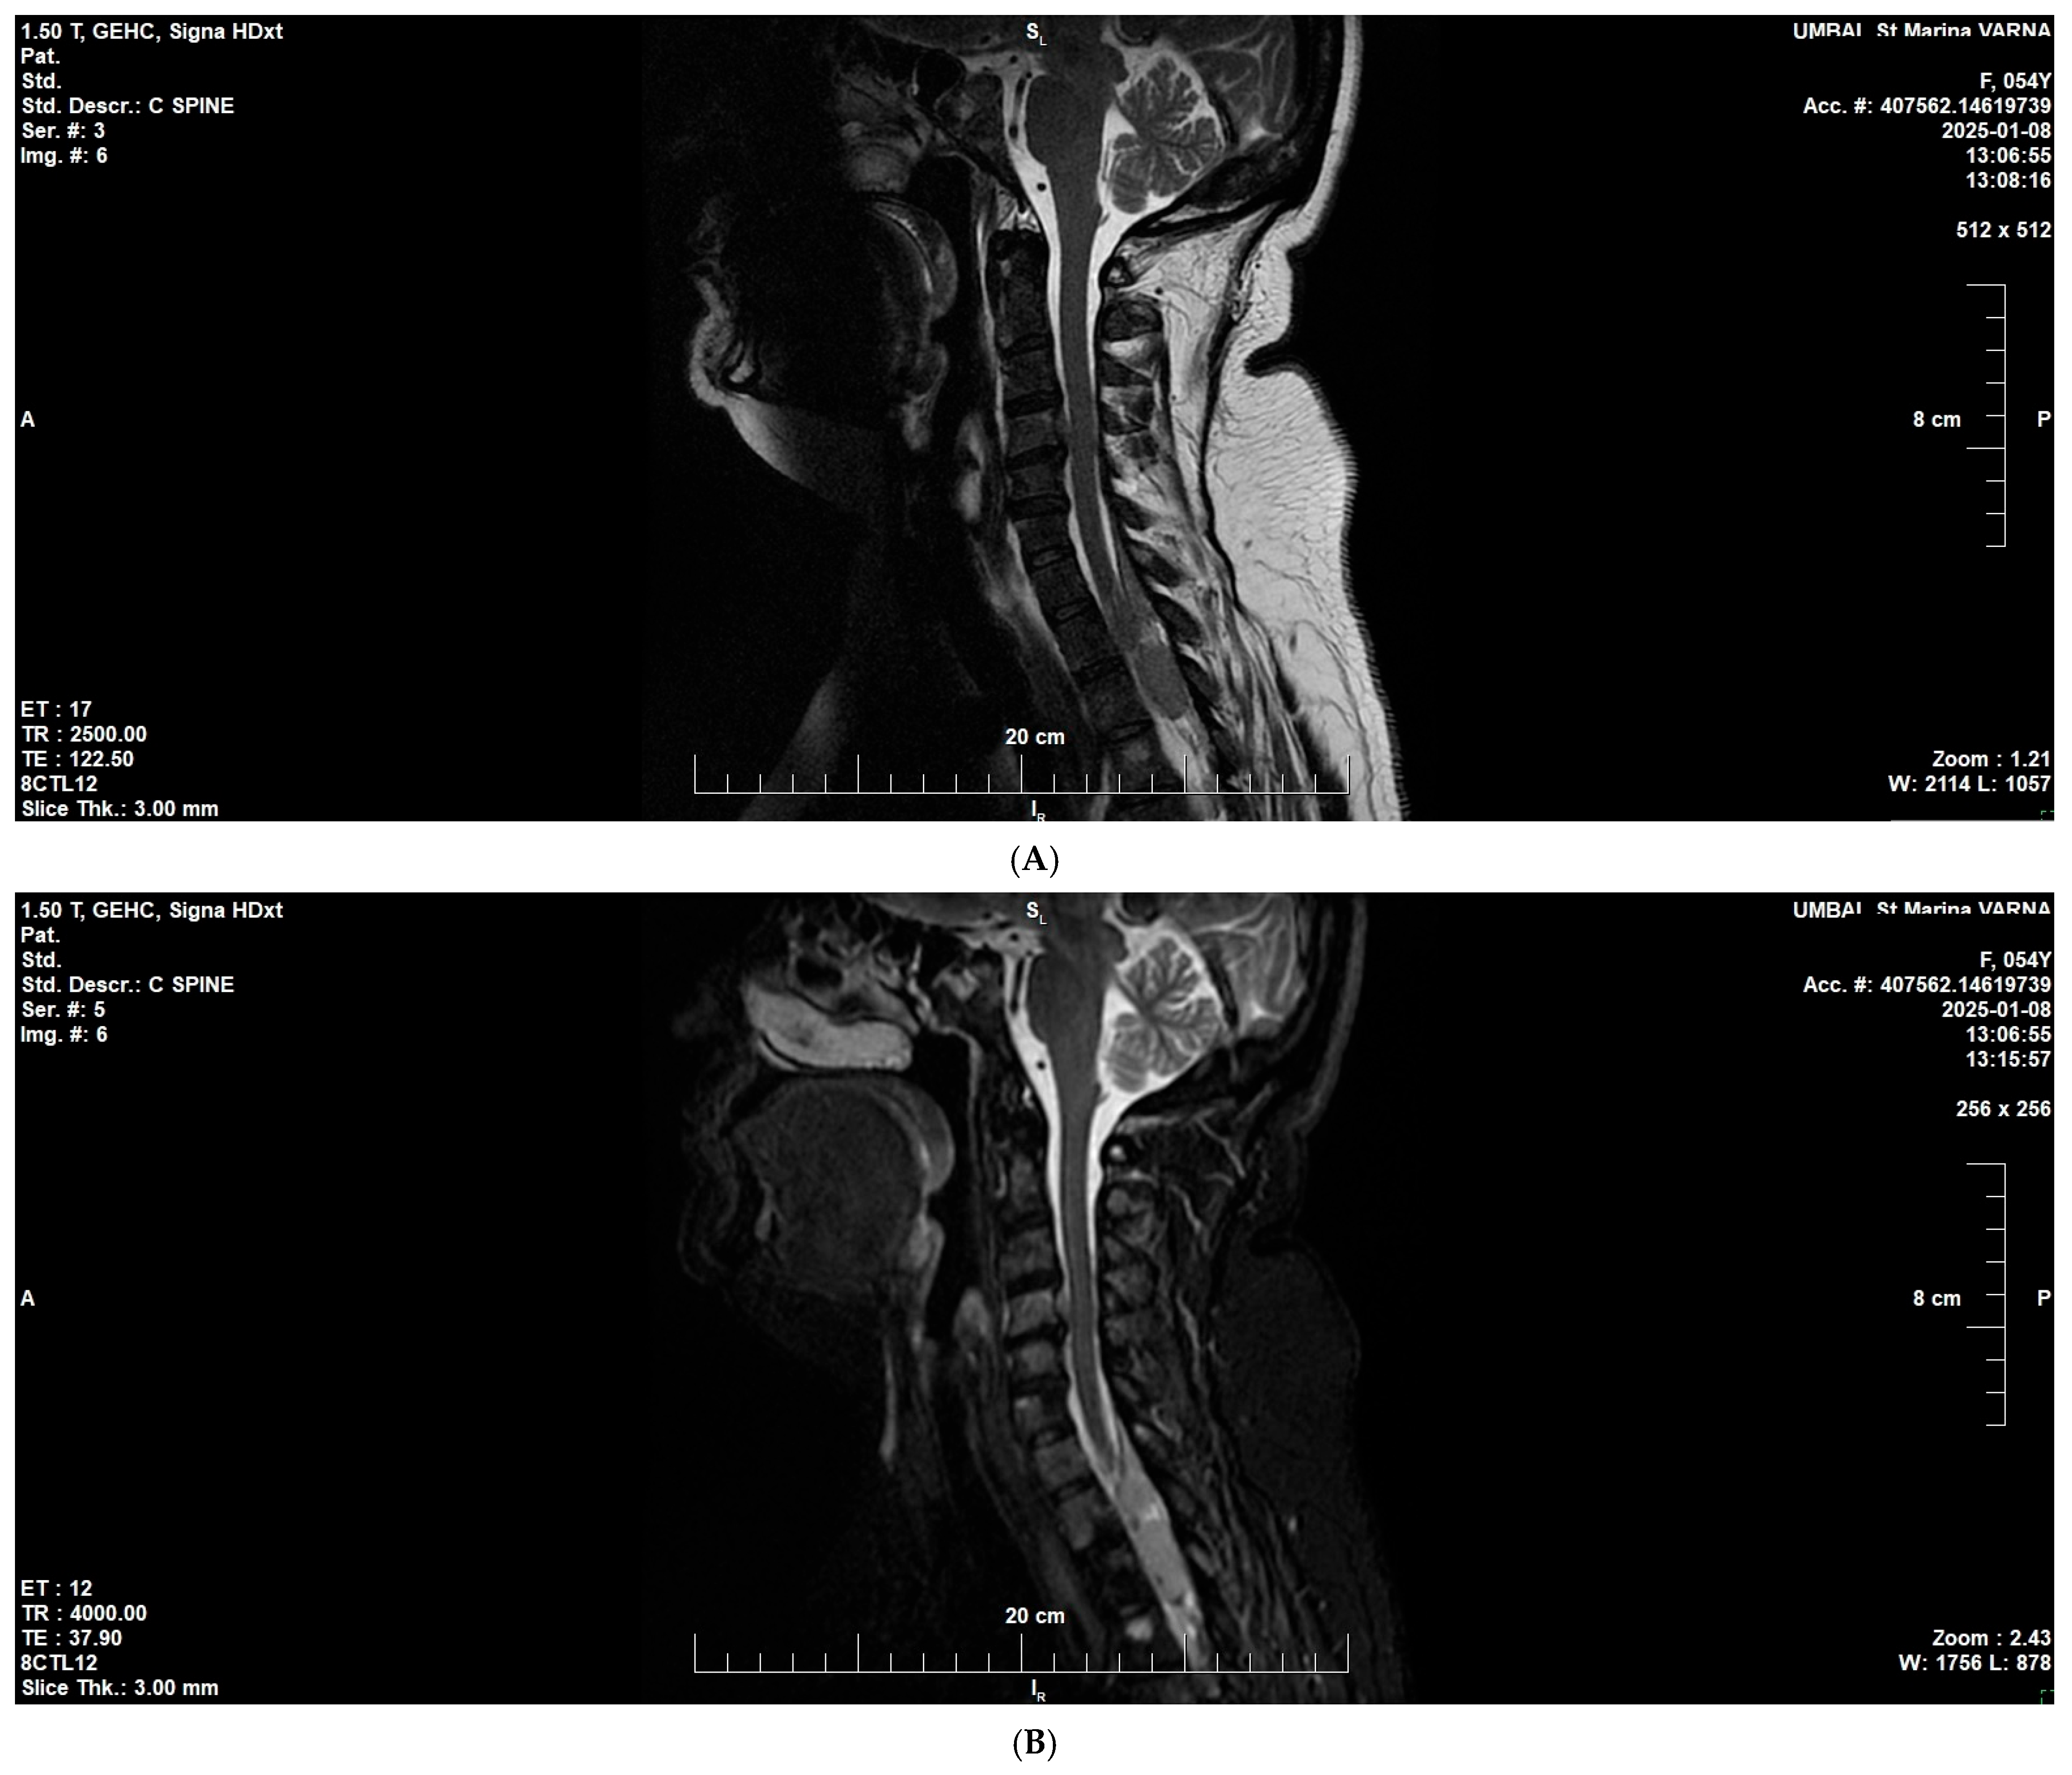

2. Case Presentation

3.4. Bone Marrow and Spine Involvement in Multiple Myeloma